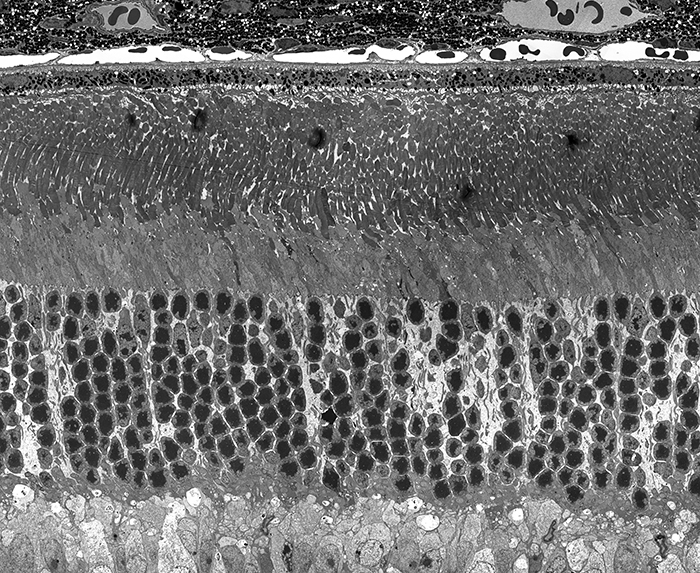

A Targeted Inhibitor Of The Alternative Complement Pathway Accelerates Recovery From Smoke-Induced Ocular Injury

Inhibition Of The Alternative pathway Of Complement Accelerates Recovery From Smoke-Induced Functional And Morphological Ocular Injury

The Alternative Complement Pathway Deficiency Amerliorates Chronic Smoked-Induced Functional And Morphological Ocular Injury

Retinal Metabolic Response to Cigarette Smoke

The Alternative Complement Pathway Mediates Functional And Morphological Deficits In A Smoke Model Of Age-Related Macular Degeneration

Retinal Metabolic Response to Cigarette Smoke